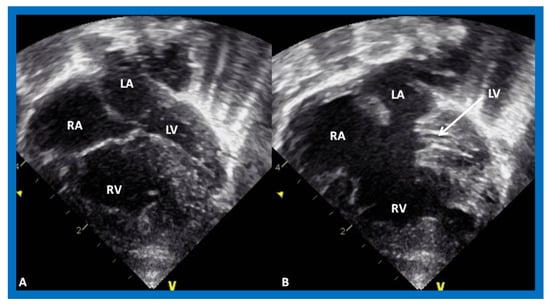

Tricuspid atresia (TA) is a cyanotic CHD and is characterized as a congenital absence or agenesis of the morphologic tricuspid valve [6,7]. The right atrium is dilated and the tricuspid valve is atretic (Figure 3). In the most common muscular variety, atretic tricuspid valve is seen as a localized fibrous thickening or a dimple in the floor of the right atrium at the anticipated site of the tricuspid valve [8,9,10,11,12]. An atrial septal defect is necessary for survival and is typically a stretched PFO. The mitral valve is usually bicuspid and morphologically a mitral valve. The LV is evidently a morphological LV, but it is enlarged and hypertrophied [8,9,10,11,12]. Usually, a ventricular septal defect (VSD) is present. The VSD is most commonly in the muscular ventricular septum [13,14]. The right ventricle (RV) is hypoplastic and is not sufficiently large in size to support pulmonary circulation. The origin of great arteries is variable and on the basis of which a classification of this disease entity was developed [6]: Type I, normally related great arteries; Type II, d-transposition of the great arteries; Type III, malpositions of the great arteries other than d-transposition; and Type IV, truncus arteriosus [6]. Some of the echocardiographic features are demonstrated in Figure 3.

Figure 3.

Echocardiograms in apical four-chamber views of an infant with tricuspid atresia demonstrating a dilated left ventricle (LV), a small right ventricle (RV), and a dense band of echoes at the site where the tricuspid valve echo should be (ATV; thick arrow). Images with closed (A) and open (B) mitral valve are shown; the tricuspid valve remains closed in both situations. A ventricular septal defect (VSD; thin arrow) is also shown. LA, Left atrium; RA, Right atrium.